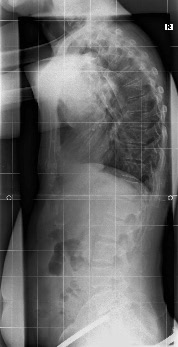

Das ist meine Röntgenaufnahme

68Grad Kyhose. .......

ich denke, aufgrund des Röntgenbildes solltest mal bei Dr. Hoffmann nachfragen, ob das ein Hohlkreuz (Hyperlordose) ist und wieviel Grad die hat. Auf jeden Fall sollte Rahmouni etwas dazu sagen können, denn er muss ja entsprechend korrigieren.

Bei der häufig vorkommenden Kombination Hyperkyphose/Hyperlordose muss man bei der aktiven Muskelpflege (ohne Korsett), wie z. Bsp. Schroth, schon darauf achten, dass man bei der Korrektur der Hyperkyphose aufgrund der Verkürzungen nicht gleichzeitig eine Hyperlordose verstärkt, ohne es zu bemerken! Deswegen immer meine Nachfrage nach einer vollständigen Diagnose.